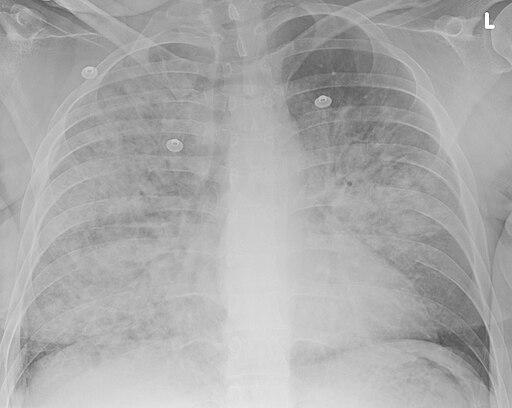

Pneumonie par aspiration

Doc James, CC BY-SA 4.0, via Wikimedia Commons

Une radiographie du thorax.